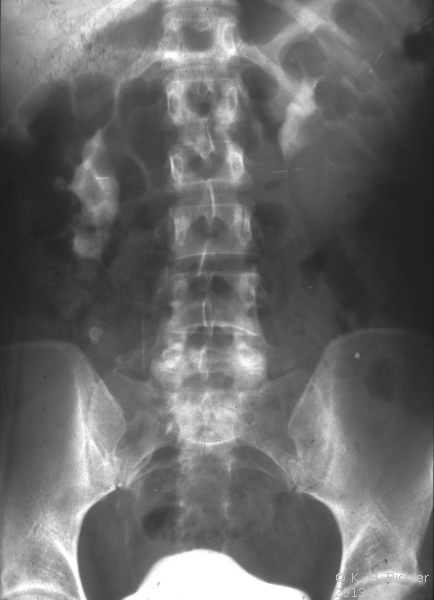

Rechtsseitige Ureterabgangsstenose mit deutlicher Hydronephrose. Behandlung mit Ureterabgangsplastik nach Anderson-Hynes (Abbildung 19).

• Abbildung 19:

2. Nach Ureterabgangsplastik